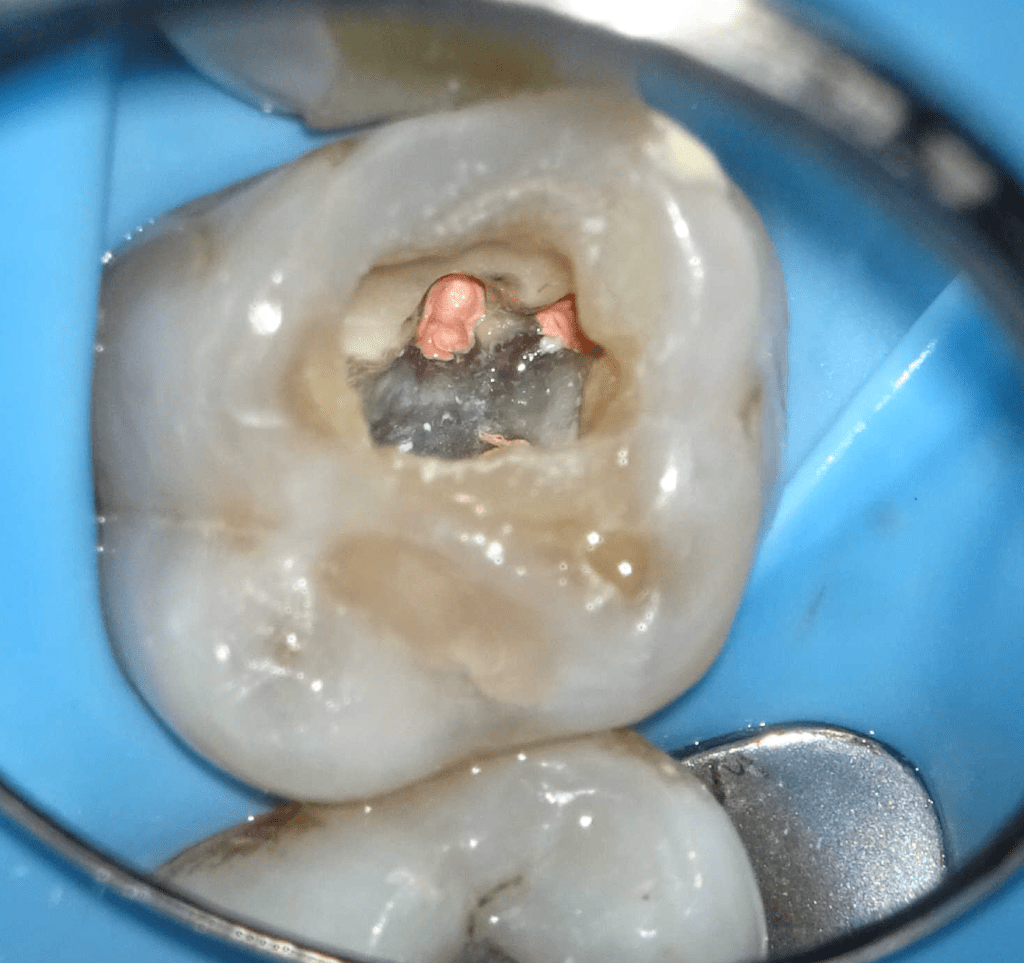

Pulpotomía biodentine + reco preendio